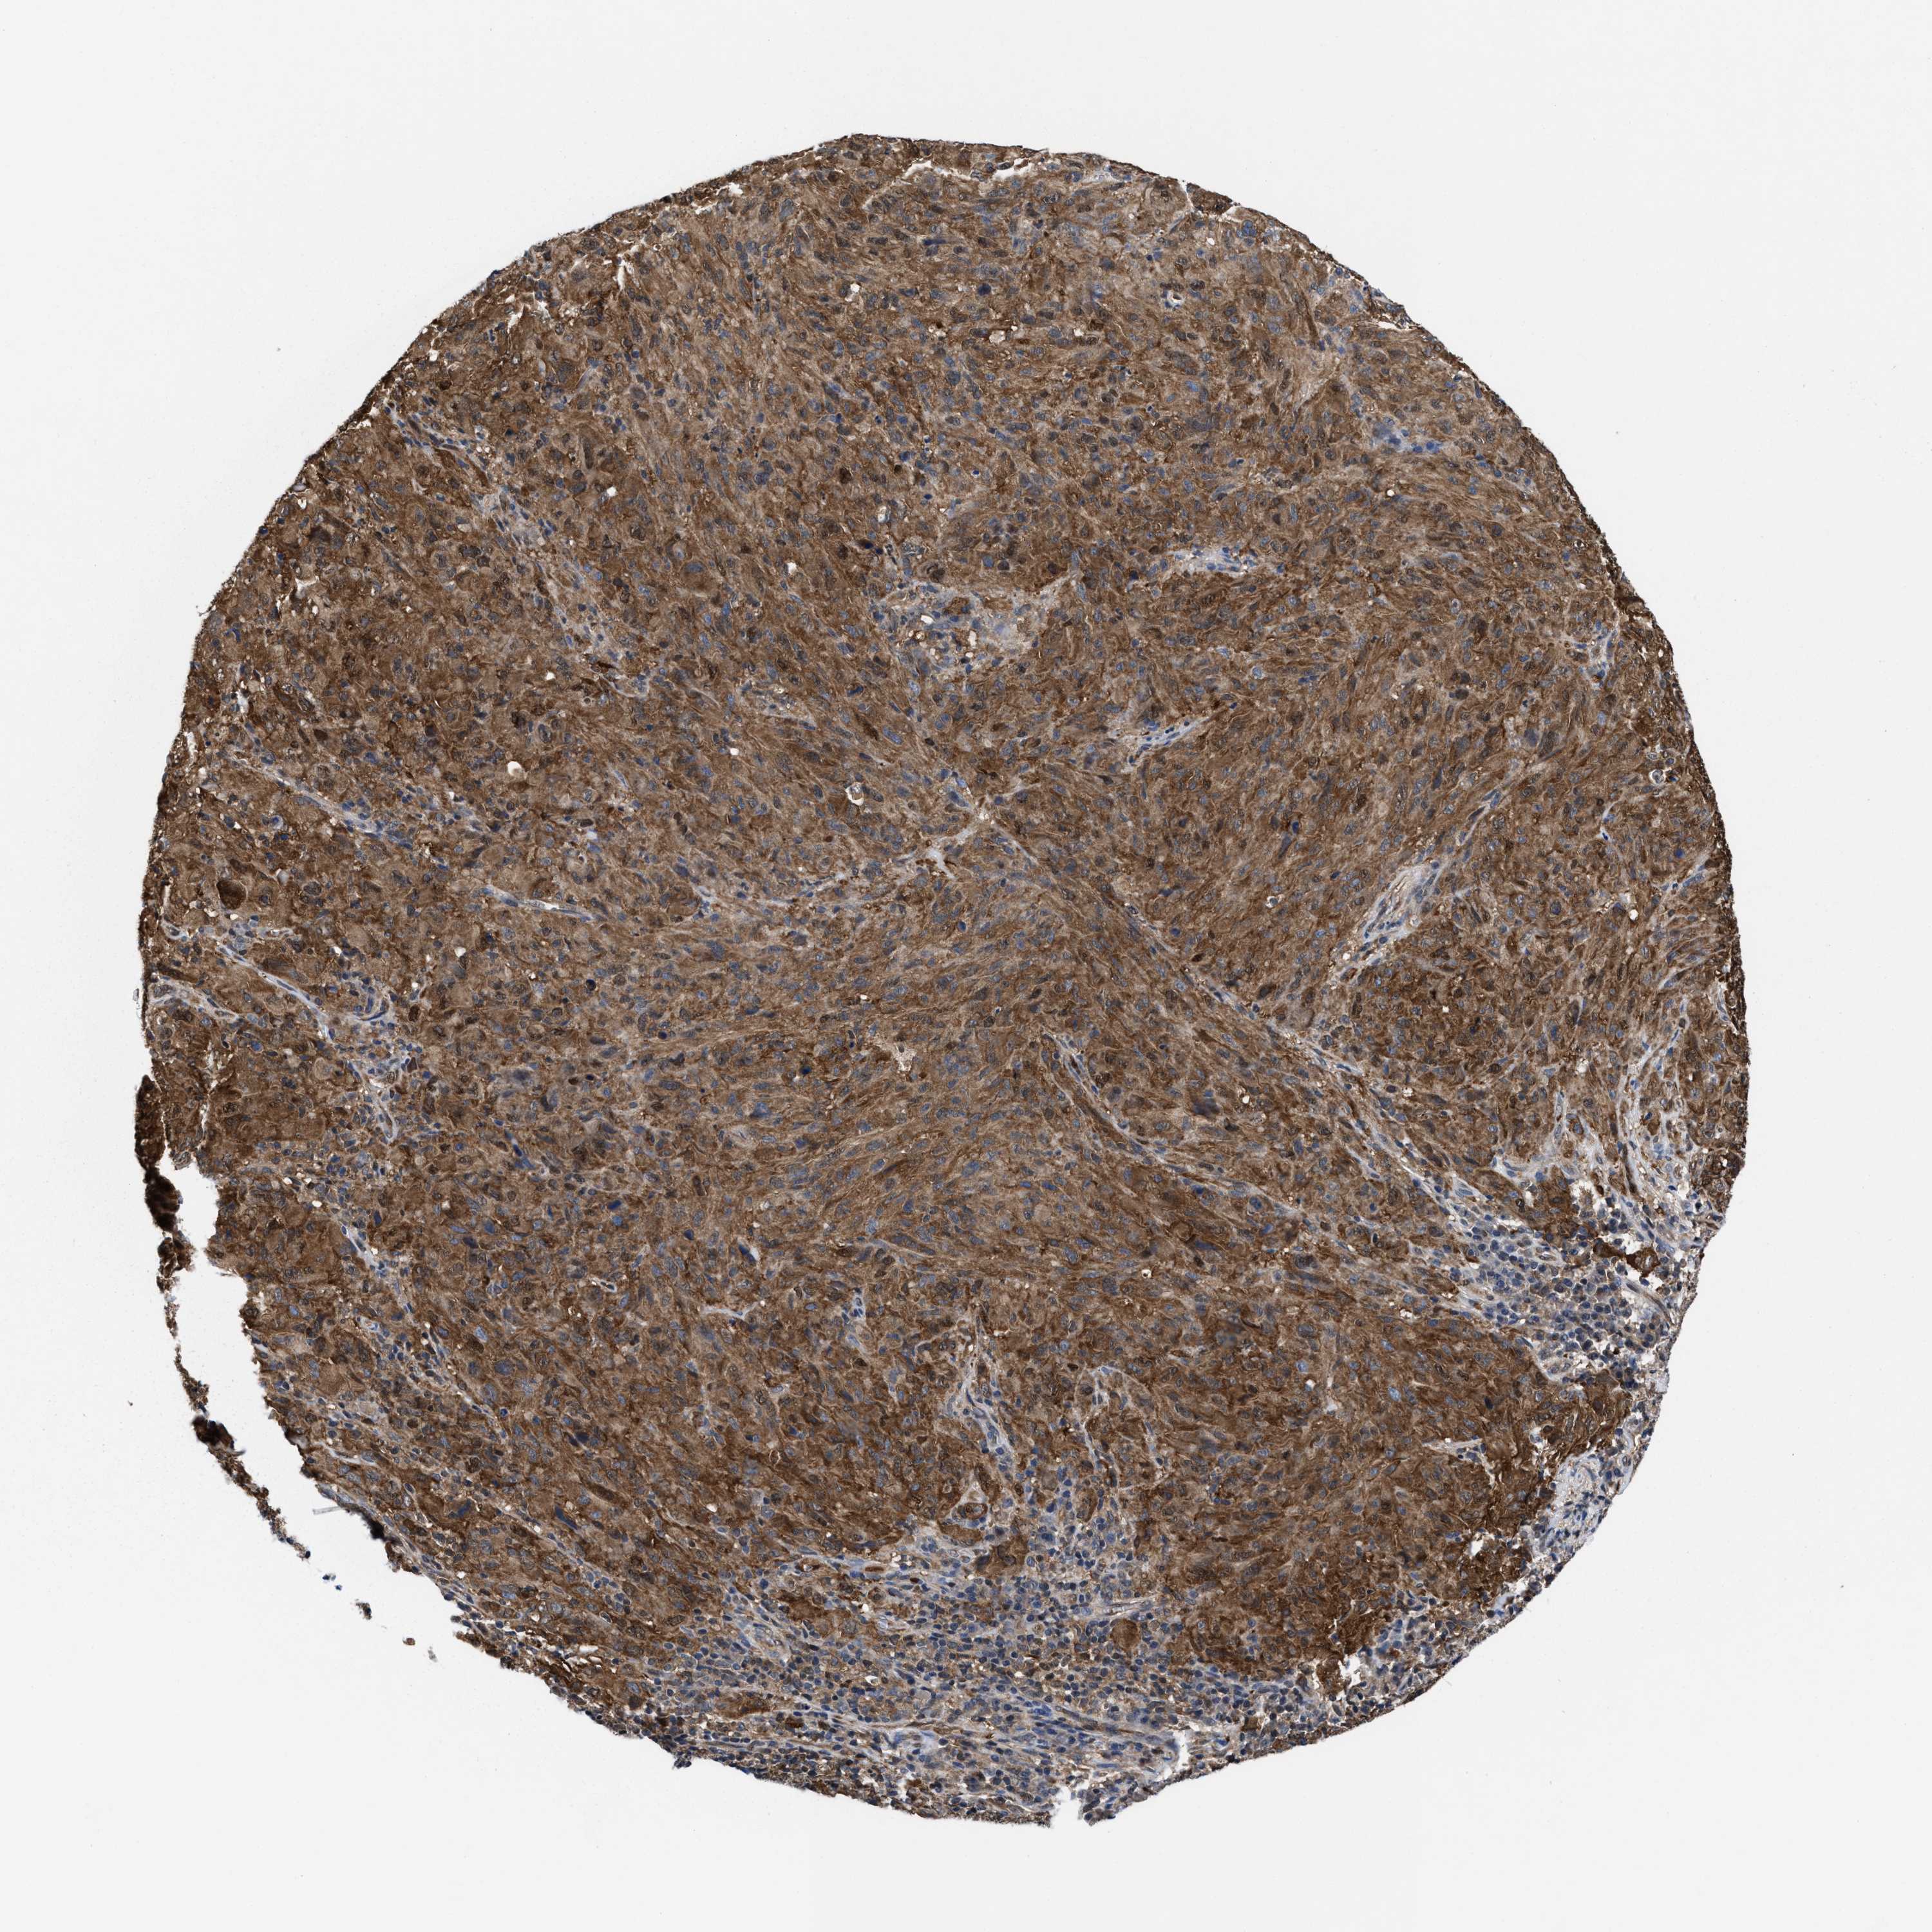

MELANOMA - Protein expressioni

A mouse-over function shows sample information and annotation data. Click on an image to view it in a full screen mode. Samples can be filtered based on level of antibody staining by selecting one or several of the following categories: high, medium, low and not detected. The assay and annotation is described here.

Note that samples used for immunohistochemistry by the Human Protein Atlas do not correspond to samples in the TCGA dataset.

Antibody stainingi

Antibody staining in the annotated cell types in the current human tissue is reported as not detected, low, medium, or high, based on conventional immunohistochemistry profiling in selected tissues. This score is based on the combination of the staining intensity and fraction of stained cells.

Each image is clickable and will lead to virtual microscopy that enables deeper exploration of all samples and also displays staining intensity scores, fraction scores and subcellular localization as well as patient and tissue information for each sample.

HPA022434

HPA022953

HPA022959

HPA028758

CAB007783

Staining

High

Medium

Low

Not detected

Intensity

Strong

Moderate

Weak

Negative

Quantity

>75%

75%-25%

<25%

None

Location

Nuclear

Cytoplasmic/membranous

Cytoplasmic/membranous,nuclear

Malignant melanoma, NOS

Malignant melanoma, Metastatic site